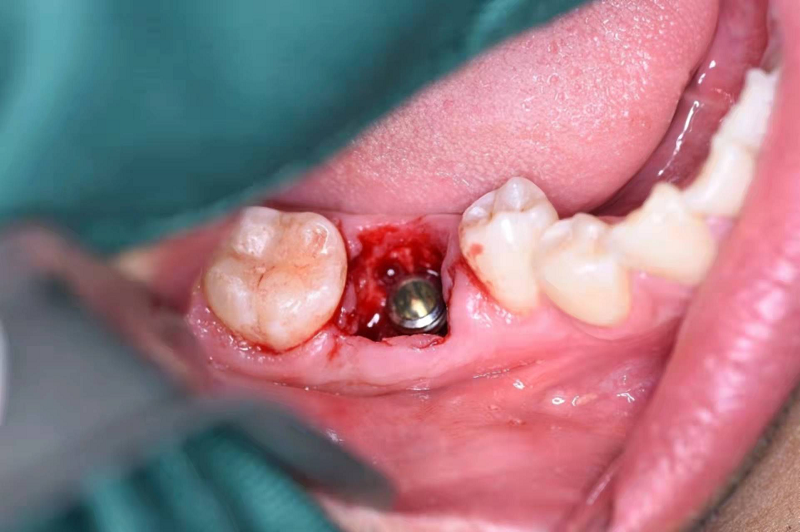

植入種植體(諾貝爾)

擰入愈合基臺: